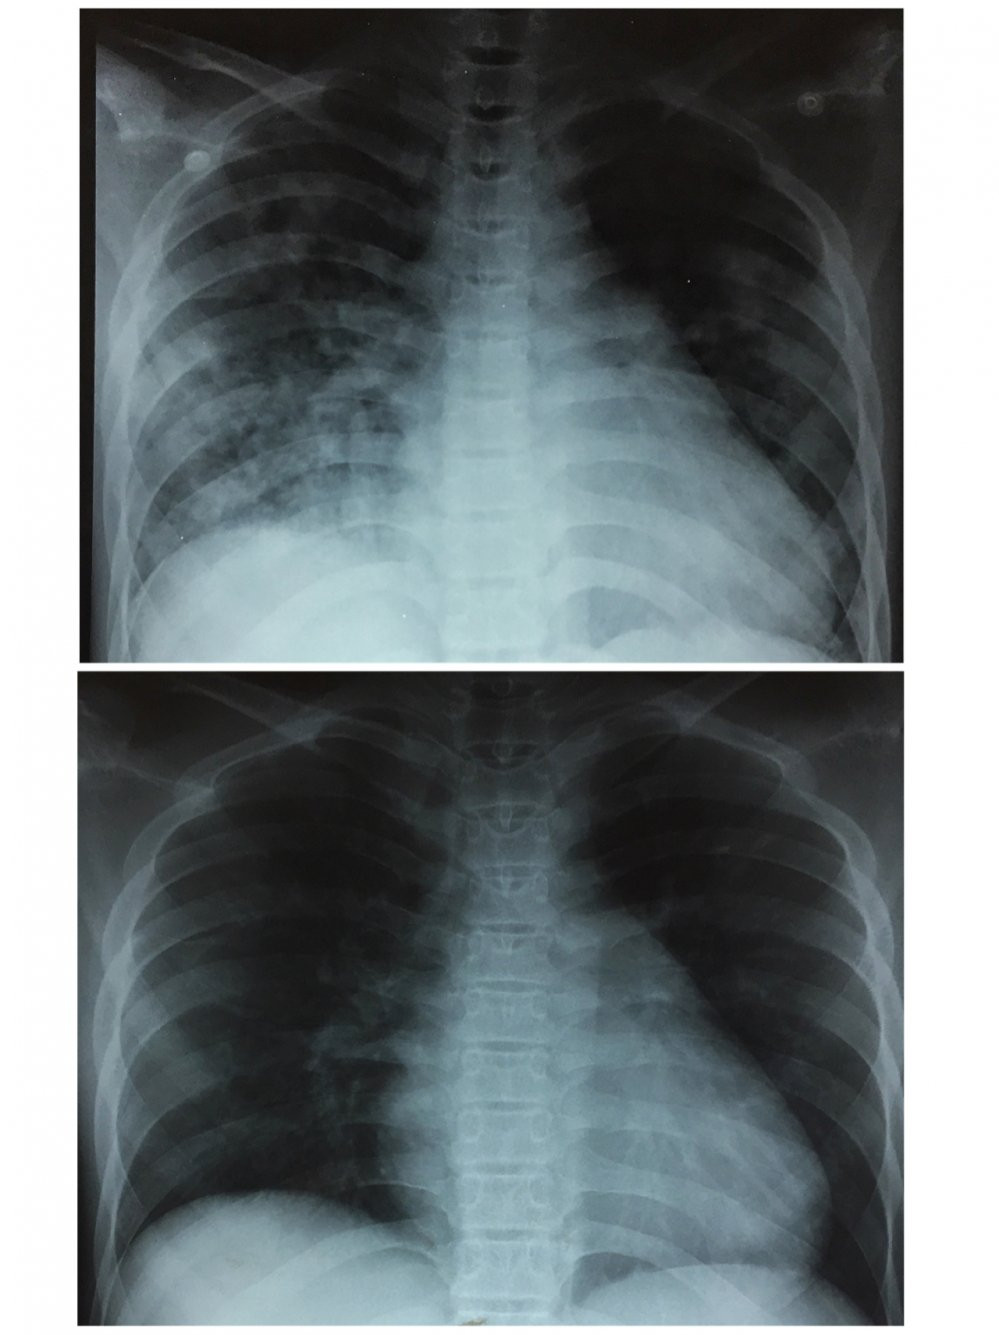

Hình ảnh chụp X-Quang phổi khi bệnh nhân vừa nhập viện khoa Cấp cứu và hình X-Quang phổi cải thiện tốt sau 3 ngày điều trị.

Sau 3 ngày điều trị, hiện tại bệnh nhân đã có thể tự thở bằng khí trời, tỉnh táo, sinh hoạt gần như bình thường, bệnh nhân chỉ còn phải tiêm kháng sinh theo phác đồ để chữa viêm phổi.